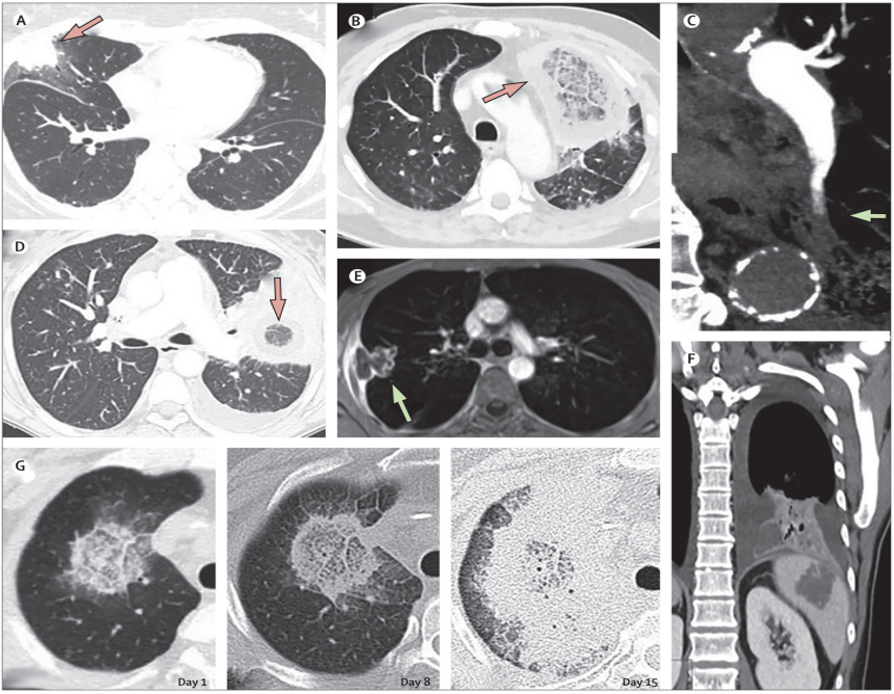

2. 肺毛霉病的诊断与监测技术—影像学

相关文献报道了肺毛霉病的影像学征象[6],从下图可以看到:【A肺毛霉病患者胸部CT上的晕轮征,结节浸润周围的磨玻璃影环,代表缺血区域,也是侵袭性肺曲霉病的典型特征(箭头)【D&B】CT上的反晕征,磨玻璃样不透明区域,周围有实变环(箭头)。【E】MRI上还可见低密度征,T1加权,肺实变或结节中的中心低密度,对应于血管阻塞引起的坏死中心区,伴有继发性肺梗死和隔离。【C】CT血管造影上的血管闭塞征,定义为局灶性病变边缘的血管中断,未描绘病变内部或病变周围的血管(箭头)。【G】CT上典型的快速进展性肺毛霉病与临床恶化有关。在疾病快速进展过程中,反晕征的范围越来越大。

对于肺毛霉病,首选的初步诊断方法是肺部CT扫描。由于肺毛霉病进展非常快,并且侵袭性非常强,也会造成血管闭塞,所以在诊断过程中,强烈建议每周进行一次CT扫描,尤其是病情不稳定的患者;如出现发热、咳嗽、咯血,需要增加增强CT扫描的密度来进一步判断患者的病情变化。表1总结了不同毛霉病人群影像学检查方法。